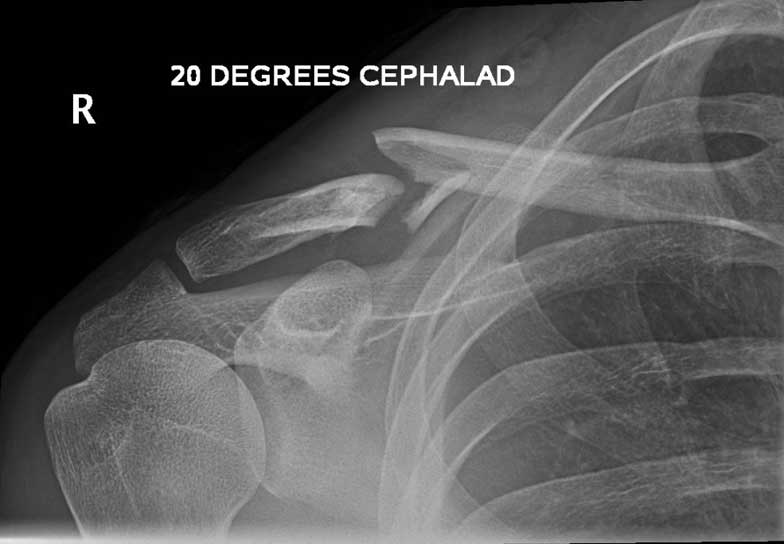

What do Distal Clavicle Fractures Look Like on X-ray and CT?

X-RAY

Click an image to enlarge